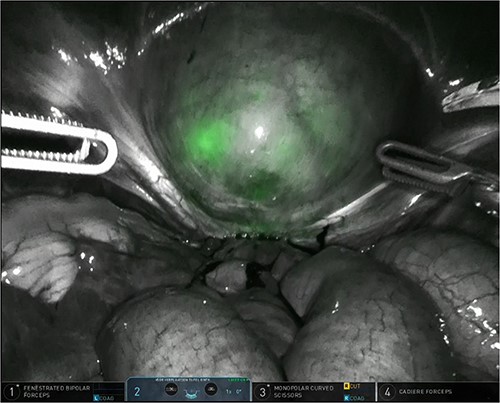

The patient was planned for a robotic resection of the endometriosis nodule and hysterectomy by an experienced robotic gynecological surgeon. The patient was placed on a PinkPad (Kebomed Europe AG) in a lithotomy position. Cystoscopy was performed with placement of ureteral stents. Double-J stents were guided up to the kidneys. Instillation of 200 ml physiologic water with 2 cc of ICG (1.9 mg/cc) in an empty bladder, with subsequent clamping of the urinary catheter (Fig. 3). The da Vinci Xi robot platform (Intuitive Surgical Inc.) was used. Instruments used were: bipolar fenestrated forceps, unipolar scissor, Cadière forceps, and Vessel Sealer Extend. Circumferential incision, dissection and detachment of the endometriotic nodule from the posterior bladder wall was performed under guidance of NIR imaging and ICG, whilst the endometriosis nodule remained stuck on the uterine isthmus (Fig. 4; Supplementary Video). During the dissection, perforation of the bladder mucosa could be avoided, with transparency of the bladder mucosa by ICG. During the hysterectomy part, the bladder catheter was unclamped. The posterior bladder wall was repaired longitudinally. The muscular layers and serosa of the bladder were sutured with Monocryl 3/0 in a two-layer closure (Fig. 5). The bladder was filled with 200 cc of physiologic water with ICG, no bladder leakage nor clear transparency by ICG of the posterior bladder wall was seen. The total operative time was 120 min. The total blood loss was 25 mL. There were no perioperative complications. The length of the hospitalization was 48 hrs. Oxybutynin was given to prevent bladder spasms from the urinary catheter and/or stents. The Foley catheter was removed after 9 days, and the ureteral stents removed after 10 days. At the 2-week outpatient visit the patient was satisfied, and didn’t experience any pain nor urinary voiding problems.

Bladder filled with physiologic water and ICG with subsequent clamping of the urinary catheter.

Robotic dissection of the endometriosis nodule between the isthmus of the uterus and bladder; lateral dissection with bilateral transparency of ICG of the thin posterior bladder wall.